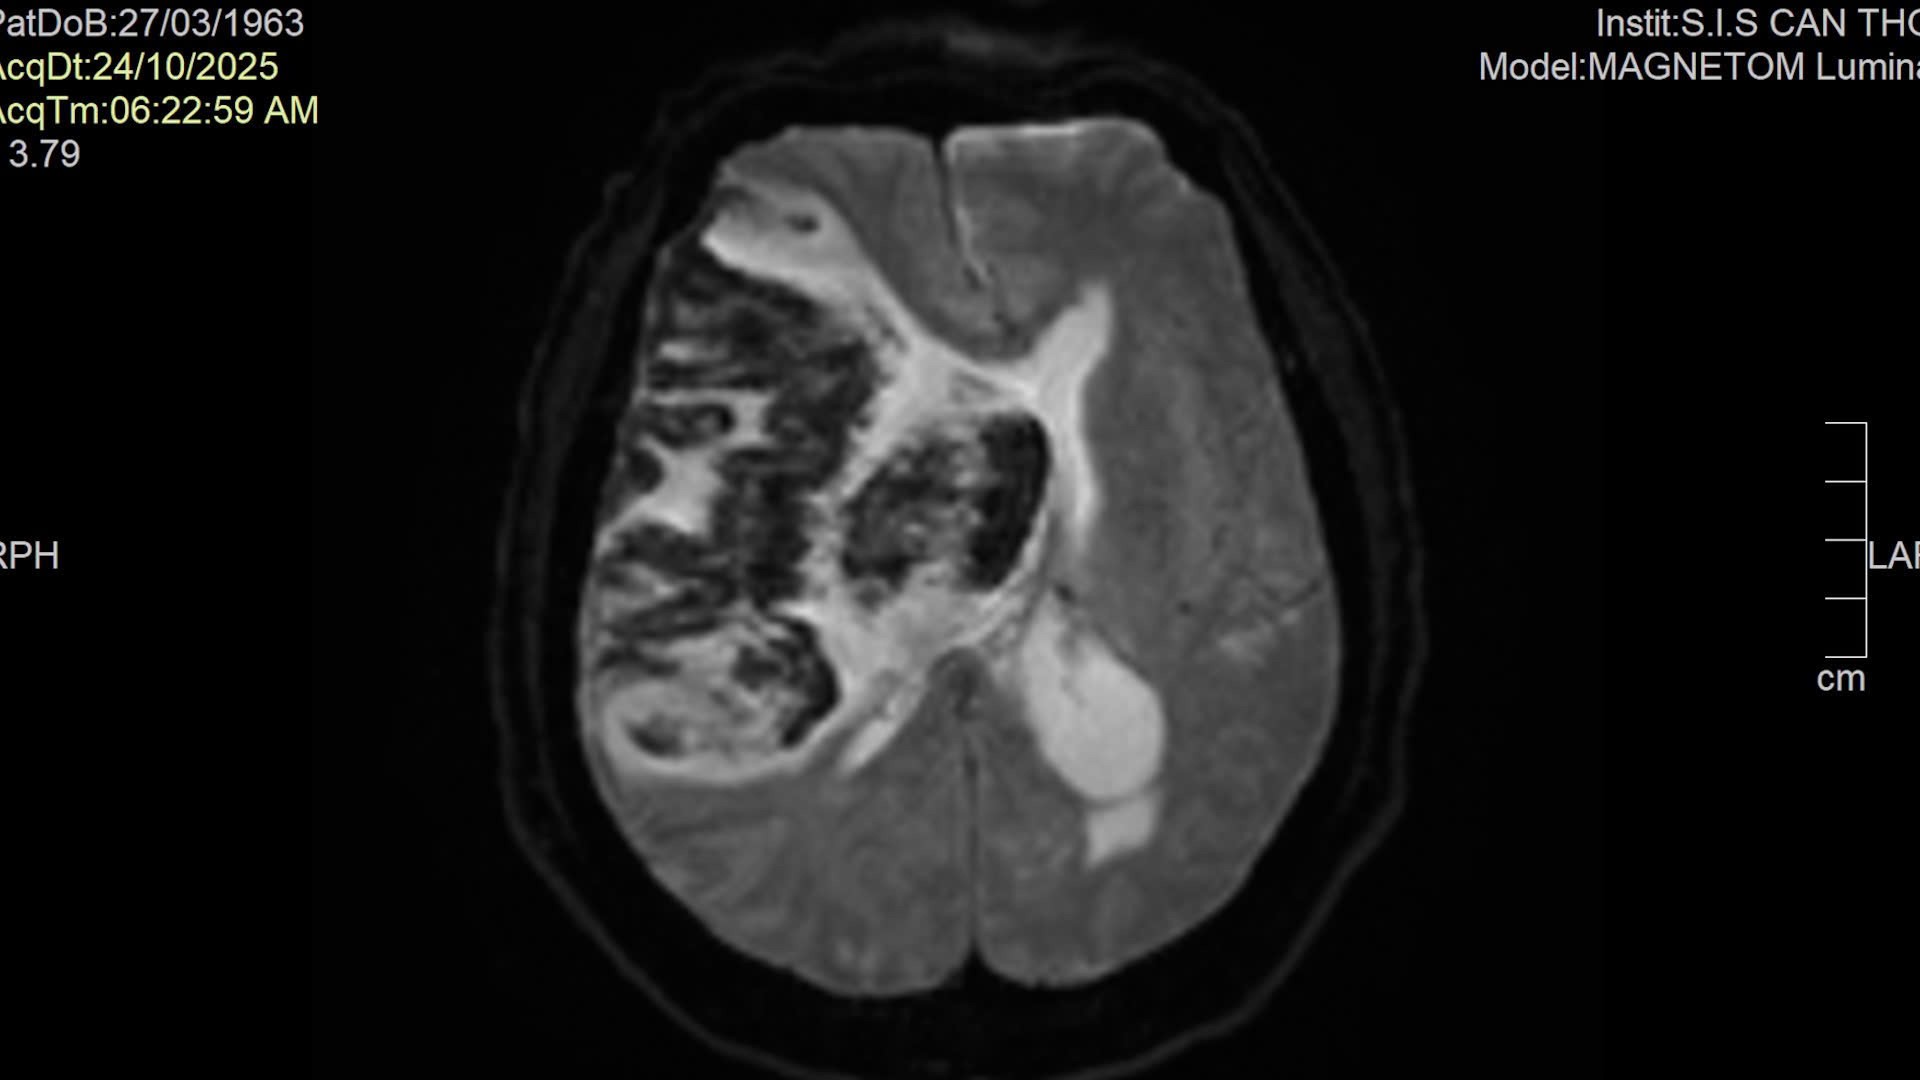

Bệnh nhân N.T.H. (62 tuổi, ngụ phường Khánh Hội, TP.HCM) nhập viện trong tình trạng hôn mê sâu (GCS 4–5 điểm), phải thở máy. Kết quả chụp MRI não cho thấy nhồi máu não diện rộng vùng bán cầu phải chuyển dạng xuất huyết, phù não nặng, kèm nhiều bệnh nền phức tạp như tăng huyết áp, đái tháo đường, rối loạn mỡ máu, bệnh tim thiếu máu cục bộ.